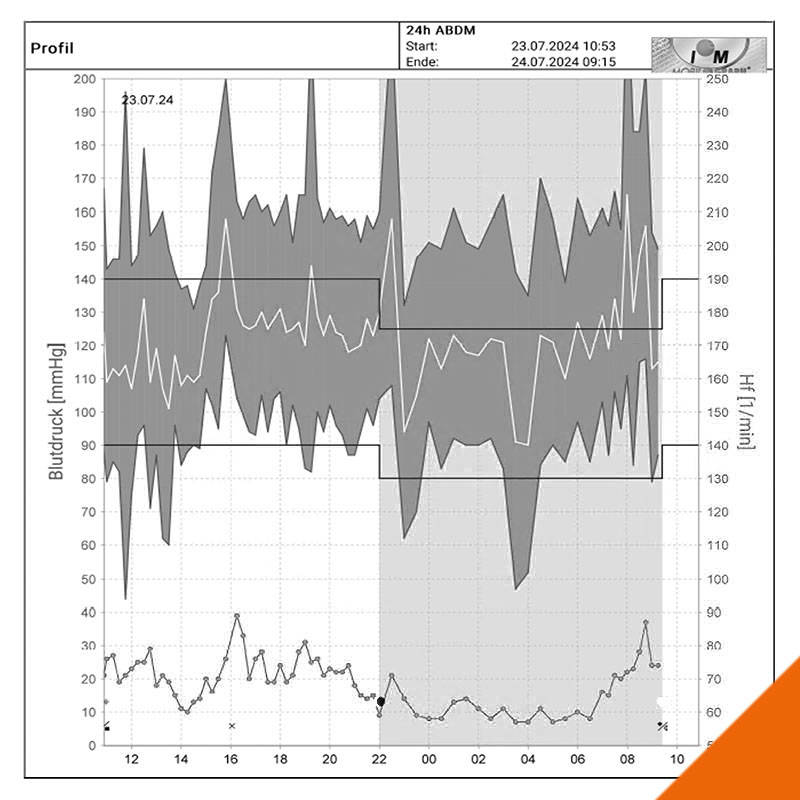

Herzinsuffizienz

Patienten mit Herzschwäche

...benötigen eine besondere Betreuung

Seit mehr als 20 Jahren widmen wir uns in unserer Praxis und in der klinischen Forschung der Früherkennung und Behandlung der Herzschwäche.

Nachfolgend erfahren Sie mehr über diese schwere und im höheren Alter zunehmend häufige Erkrankung, die enormen jüngsten Fortschritte bei der Behandlung, aber auch die Herausforderungen für Patienten, Angehörige und Behandlungsteams.